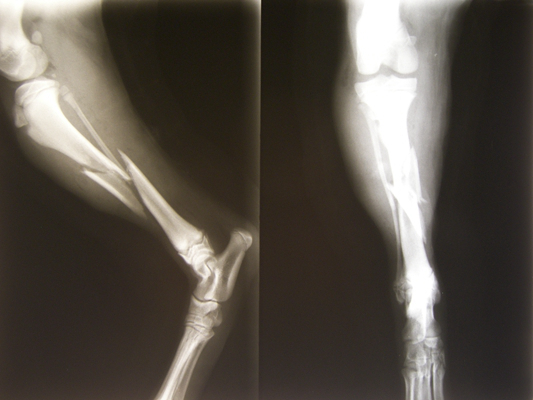

骨折圖片

骨裂